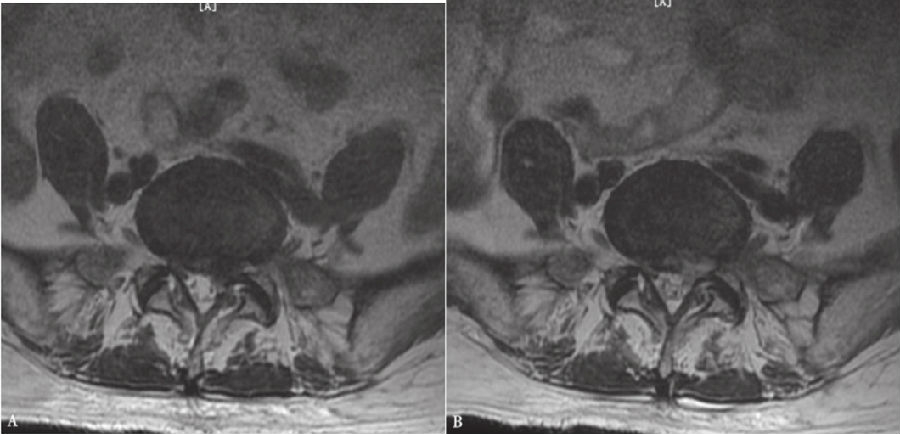

纤维环完全破裂,髓核突向椎管,仅有后纵韧带或一层纤维膜覆盖,表面高低不平。此类型常需手术治疗。(图1)

图1 腰椎磁共振显示中央突出型的L4-5椎间盘